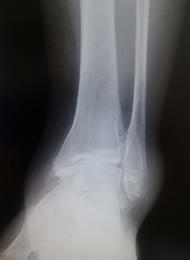

変形性足関節症

変形性足関節症は、足関節の表面に覆われている軟骨がすり減ってしまう疾患です。骨折や繰り返す捻挫など外傷によって起こることが多いと言われています。歩行時に軟骨のすり減っている部分に疼痛が生じます。また病態が進行すると、外観上も足の変形が認められます。

変形の程度が軽い場合は、足底挿板や鎮痛薬内服による治療を行います。痛みが強い場合や変形が強い場合は、主に関節固定術を行います。適応となる患者さんは限られていますが、足関節の可動域を温存するため、脛骨低位骨切り術や人工足関節置換術を行うこともあります。

当院では、膝関節や股関節などの下肢全体のアライメントを含めて、痛みの原因を追究し、手術療法を決めるようにしています。従来は足関節前方を大きく切開して行う方法が行われていましたが、手術後の痛みや傷が大きくなることが問題でした。当院では患者さんへの侵襲を減らすため、皮膚切開を大きく行わない関節鏡視下関節固定術を積極的に導入しています。

![]() 変形性足関節症の 単純レントゲン写真 |

![]() 鏡視下固定術術後 |